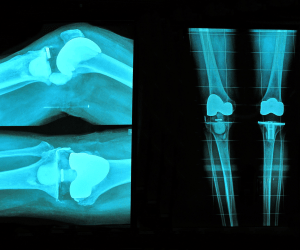

- sklepna špranja je na RTG sliki močno zožena, kost pod hrustancem pa sklerotična (okorela).